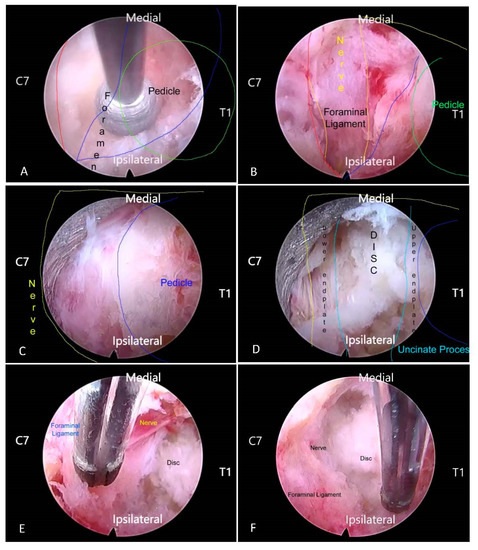

2.2. Surgical Technique—Partial Pediculotomy and Partial Vertebrotomy Posterior Endoscopic Cervical Decompression

- Kim, H.S.; Wu, P.H.; Lee, Y.J.; Kim, D.H.; Kim, J.Y.; Lee, J.H.; Jeon, J.B.; Jang, I.T. Safe Route for Cervical Approach: Partial Pediculotomy, Partial Vertebrotomy Approach For Posterior Endoscopic Cervical Foraminotomy and Discectomy. World Neurosurg. 2020, 140, e273–e282. [Google Scholar] [CrossRef] [PubMed]